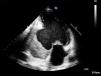

As imagens apresentadas são de um homem de 62 anos, fumador, sem antecedentes de cardiopatia, internado no nosso hospital por pneumonia adquirida na comunidade. A radiografia torácica da admissão mostrava cardiomegalia e o eletrocardiograma tinha ondas Q nas derivações inferiores. O ecocardiograma transtorácico mostrou dilatação ligeira das cavidades esquerdas, depressão severa da função sistólica ventricular esquerda, evidenciando-se uma formação aneurismática envolvendo a porção basal das paredes posterior, inferior e lateral, com 8 cm de diâmetro e que continha trombo (Figuras 1 e 2). Não foi possível, através desta técnica, um diagnóstico diferencial inequívoco entre aneurisma e pseudonaeurisma, pelo que se realizou ressonância magnética, que revelou enfarte inferior antigo extenso, com extensão à porção adjacente do ventrículo direito, com rutura miocárdica na parede inferior. Estabeleceu-se assim o diagnóstico de pseudoaneurisma localizado às paredes inferior e posterior, com trombo organizado no seu interior (Figuras 3 e 4). O cateterismo cardíaco revelou doença de um vaso com oclusão crónica ao nível do segmento médio da coronária direita. Foi proposta correção cirúrgica, que o doente recusou. Manteve-se clinicamente estável em classe NYHA II até ao 10.° mês de seguimento após internamento, tendo posteriormente abandonado a consulta.